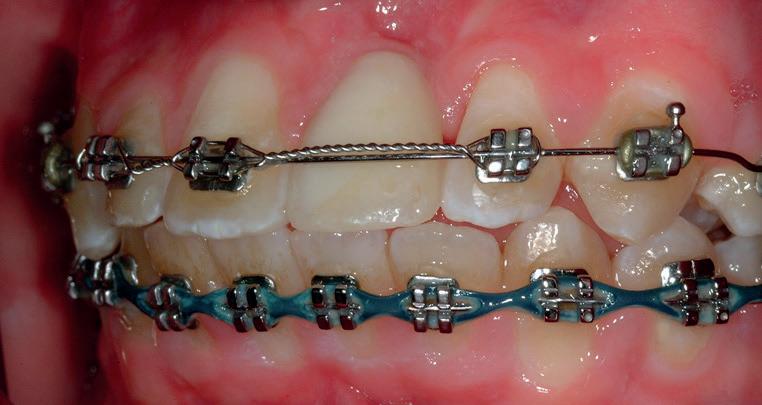

RECONFIGURAREA suportului osos implantar. În cazul prezentat, după ani de terapie ortodontică incorect executată, dezvoltarea dentară a pacientului a complicat obținerea unui zâmbet estetic. S-a reanalizat și s-a optat pentru abordare interdisciplinară care cuprinde chirurgia parodontală, un al doilea tratament

ortodontic și protetica pentru a oferi îngrijirea comprehensivă.